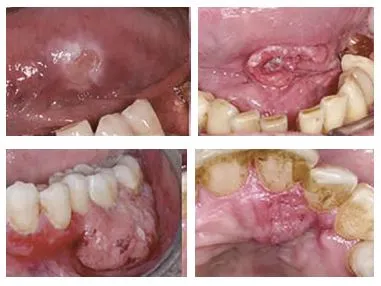

구강암 -07.JPG 사진4. 구강암을 의심할 만한 구강내 다양한 병소들